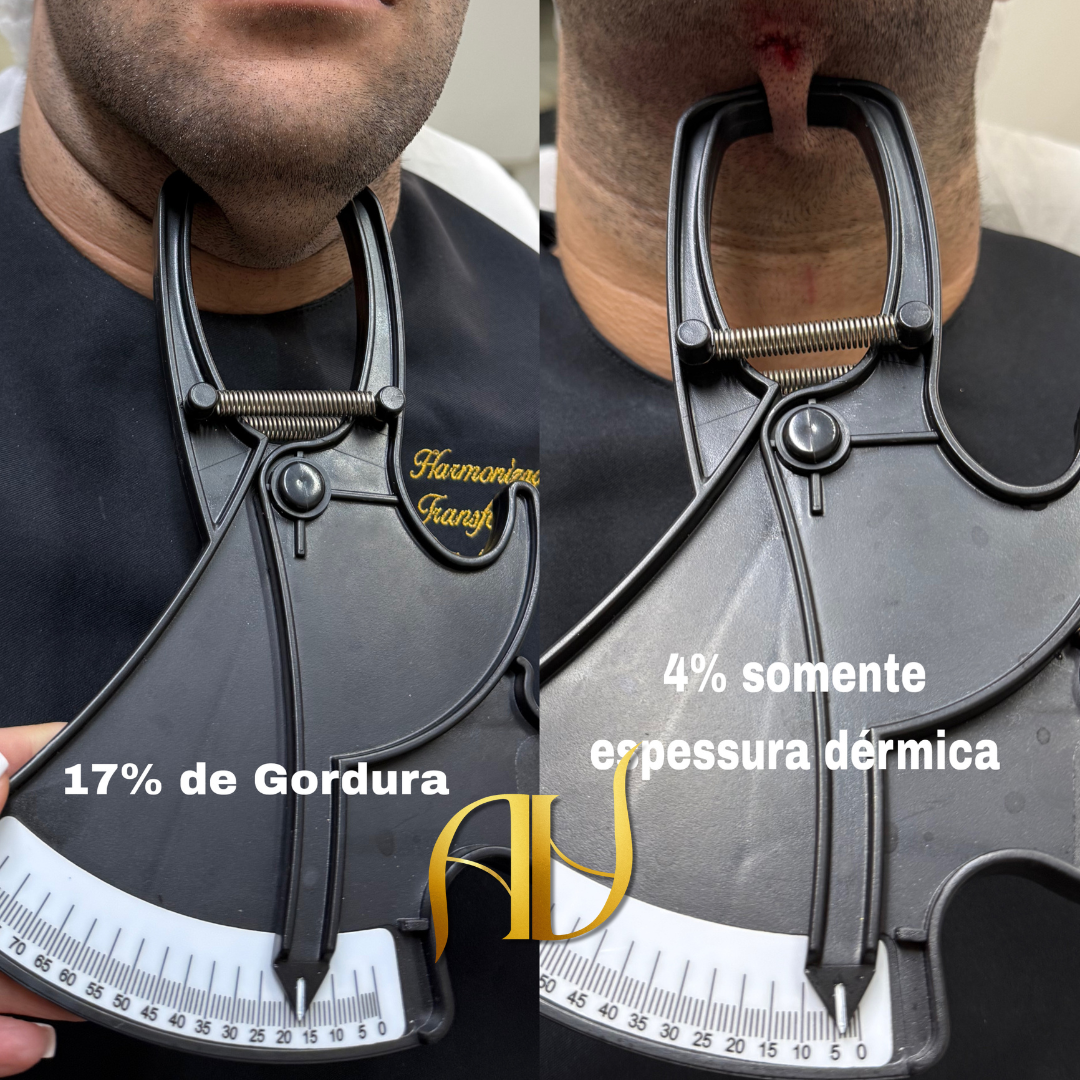

Lipoaspiração Cirúrgica da Gordura Submentoniana: Técnica HD Master

Procedimento minimamente invasivo realizado pela Dra. Ana Paula, especialista em harmonização facial, com foco em resultados naturais e seguros.

Procedimento realizado após avaliação facial

Técnica avançada e personalizada

Recuperação rápida

Resultados progressivos e naturais

Você se identifica com alguma dessas situações?

A papada aparece muito nas fotos

Mesmo emagrecendo, a gordura abaixo do queixo permanece

O rosto parece mais pesado ou sem definição

Você sente que a papada envelhece seu rosto

Se você respondeu sim para alguma dessas situações, a lipo de papada pode ser uma solução indicada para seu caso.

Lipo de papada funciona em qualquer pessoa?

É indicada para pessoas com acúmulo de gordura localizada abaixo do queixo. A avaliação identifica se a lipo enzimática é o melhor tratamento para o seu caso específico.

A lipo de papada funciona mesmo para definir o contorno facial?

Sim. A lipo de papada reduz a gordura localizada abaixo do queixo e traz mais definição para o contorno facial. É um dos procedimentos mais buscados pela clínica e os resultados começam a aparecer nos primeiros dias.